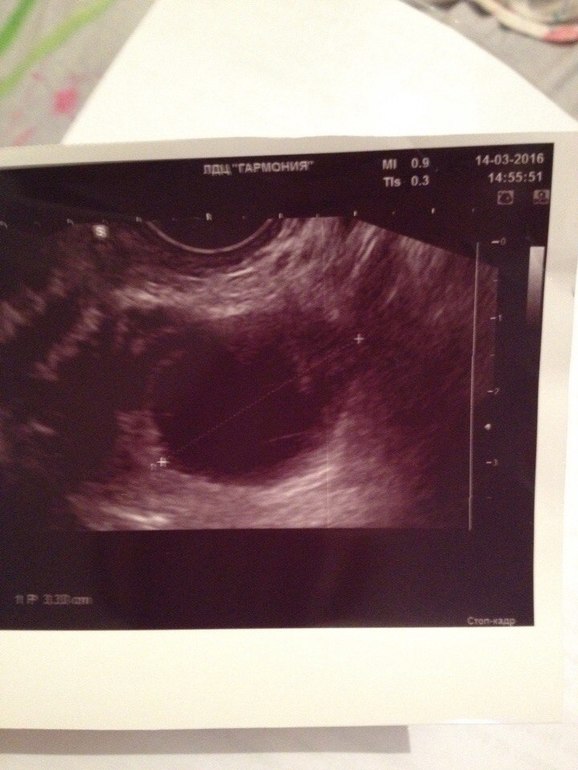

Мед.обследования и БТДевочки, сказал узист, что это фолликулярная киста. меня смущает неоднородность по узи. что думаете?

Если правильно вижу размеры-33мм(3,38см), то это не лопнувший доминантный фолликул, который перешел в фолликулярную кисту(функциональную). Овуляции не было. С началом месячных такие кисты проходят

Ну либо большой фолликул, ибо уже кистозное образование. А что же это еще может быть?